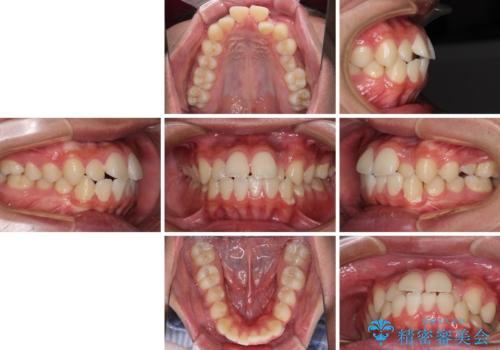

- 前歯のデコボコと口元の突出感を気にして来院された患者様です。

上下前歯がくちばしのように突出していたため、上下左右の第一小臼歯4本を抜歯し、ワイヤー装置にて矯正治療を行うこととしました。

左上は第二小臼歯が90度捻れており、状態が良くない歯であったため、左のみ第二小臼歯を抜歯することとしました。

第二小臼歯抜歯により治療期間が長くなることを了承いただき、治療を開始しました。